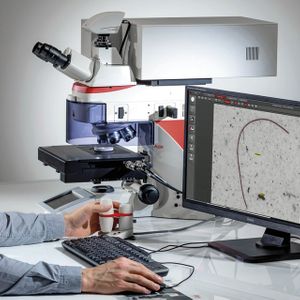

FEB 09, 2024CancerHistopathology describes the process of examining pieces of tissue using a microscope. Light microscopic (LM) exam ...